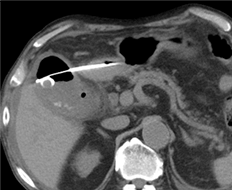

CTで膵頭部腫瘤を指摘

EUS-FNAで組織採取

採取された検体

膵癌と診断